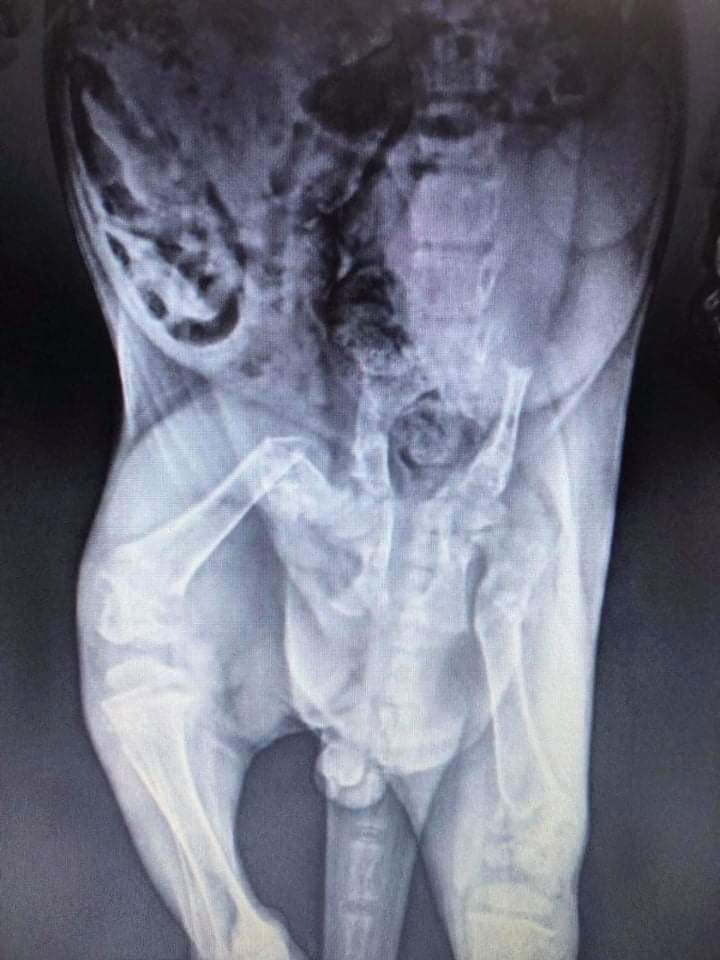

Maja (bo takie imię dostała na nowy start) jest już po tomografii komputerowej oraz konsultacjach z najlepszymi specjalistami. - Musimy poczekać z operacją bo koteczka ma dopiero 4-5 miesięcy, a operacja może jej bardziej zaszkodzić niż przynieść korzyści. Robimy wszystko, by przywrócić jej sprawność - mówi Katarzyna.